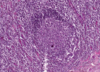

מה מסומן במס 2 בתמונה?

Germinal center

Lhymph nodule בתוך ה

מסומן במס 2 בתמונה

המוקד בו לימפוציטים מסוג B

מתחילים את תהליך הדיפרנציאציה והפרוליפרציה שלהם

Lympth nodule איך קוראים למרכז הבהיר ב

Germinal center

מסומן במס 2 בתמונה

המוקד בו לימפוציטים מסוג B

מתחילים את תהליך הדיפרנציאציה והפרוליפרציה שלהם

Germinal center מהו

מסומן במס 2 בתמונה

Lympth nodule המרכז הבהיר ב

המוקד בו לימפוציטים מסוג B

מתחילים את תהליך הדיפרנציאציה והפרוליפרציה שלהם

איך קוראים למבנה ההסטולוגי המסומן במס 3?

Corona

Germinal center מסביב ל

(CAP אם האיזור לא יקיף את כל הזקיק הוא ייקרא)

Corona מהו המבנה ההיסטולוגי ?

מבנה ההסטולוגי המסומן במס 3

Germinal center מסביב ל

(CAP אם האיזור לא יקיף את כל הזקיק הוא ייקרא)

מה בתמונה?

lymphatic node

קשר לימפה